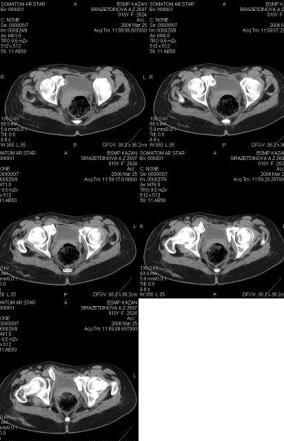

Предоставляю срезы. Если пациентку функционально ничего не беспокоит, стоит ли навязывать ей лечение.